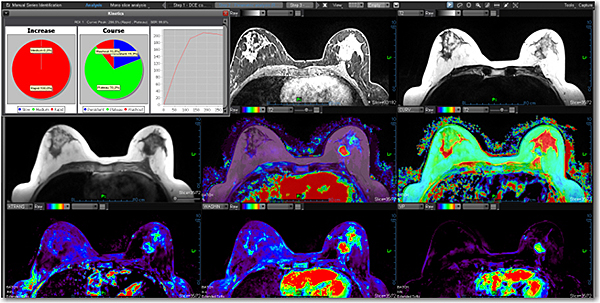

Додаток Breast Streamlined.

Додаток Breast Streamlined*- це ефективний інструмент для виявлення, характеристики та постановки діагнозу для утворень молочної залози. Цей додаток обчислює та відображає звичайні, дифузійні та кінетичні карти (якісні) та пропонує повний мультипараметричний аналіз, включаючи MPR та 3D візуалізацію, сегментацію об'єму, синтез кількох серій, кінетику та аналіз кривих. До Breast Streamlined також входить остання версія протоколу на основі BI-RADS® ATLAS. Цей пакет є корисним для поліпшення комунікації між рентгенологами, пацієнтами та направляючими лікарями. Стандартний інструмент звітності забезпечує хорошу оцінку ризику та спостереження за підозрілими знахідками.